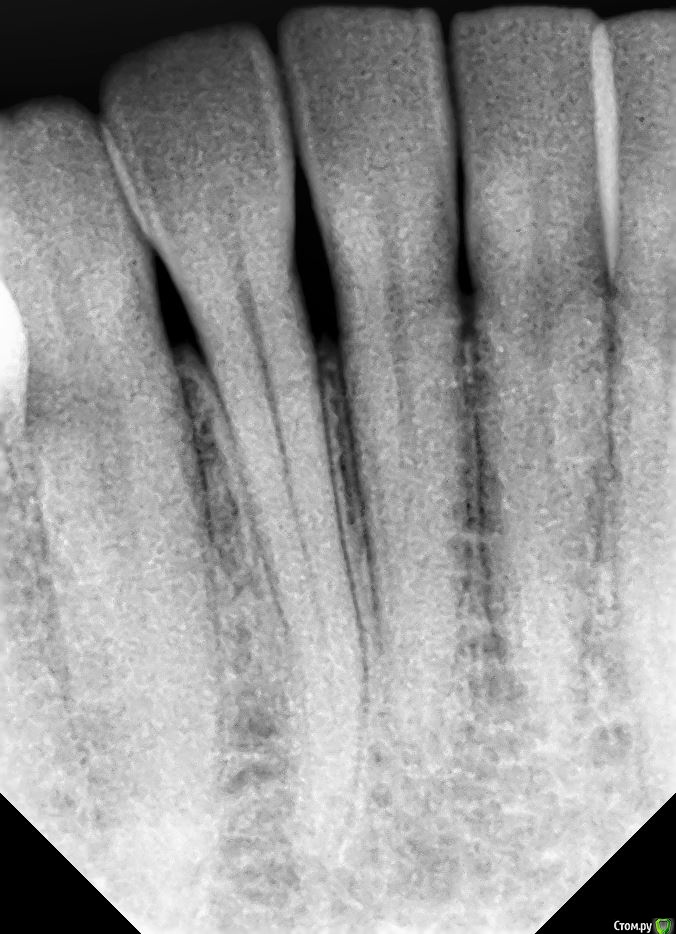

kramer Опубликовано 8 января, 2021 Поделиться Опубликовано 8 января, 2021 Нужны прицельные снимки с установленными коронками Ссылка на комментарий

Diana1974 Опубликовано 9 января, 2021 Автор Поделиться Опубликовано 9 января, 2021 Нужны прицельные снимки с установленными коронкамиПрикладываю Ссылка на комментарий

kramer Опубликовано 9 января, 2021 Поделиться Опубликовано 9 января, 2021 еда очень сильно набивается Где именно, уточните вызывает сильное давление и боль, жесткая еда и холод вызывают пульсацию Больше возле дальнего имплантата или ближнего? Ссылка на комментарий

Diana1974 Опубликовано 9 января, 2021 Автор Поделиться Опубликовано 9 января, 2021 Где именно, уточните Больше возле дальнего имплантата или ближнего? Больше всего застревает со стороны языка в промежутке между коронками, туда еда попадает так, что очень сложно достать без промывки ирригатором и нити, и соответственно находясь вне дома еда очень здорово раздражает десну (может это нормально, но я думала, что можно будет полноценно всё есть не зная боли).По поводу боли не могу определенно сказать, что она исходит от конкретной коронки, но она совершенно четко присутствует вне приемов пищи. Ссылка на комментарий

kramer Опубликовано 9 января, 2021 Поделиться Опубликовано 9 января, 2021 Попросите врача проверить все зубы вверху и внизу с этой стороны на предмет пульпита, раз вы говорите, что еще в июле появилось. Ссылка на комментарий

Diana1974 Опубликовано 9 января, 2021 Автор Поделиться Опубликовано 9 января, 2021 Попросите врача проверить все зубы вверху и внизу с этой стороны на предмет пульпита, раз вы говорите, что еще в июле появилось. Скриншоты, которые я приложила в первом сообщении взяты из кт от 23 декабря, врач тогда сказал, что мы его как раз и делаем, чтобы еще раз перепроверить все зубы, долго смотрел и сказал всё хорошо, разве что на дальнем зубе можно переделать запломбированные каналы. Ссылка на комментарий